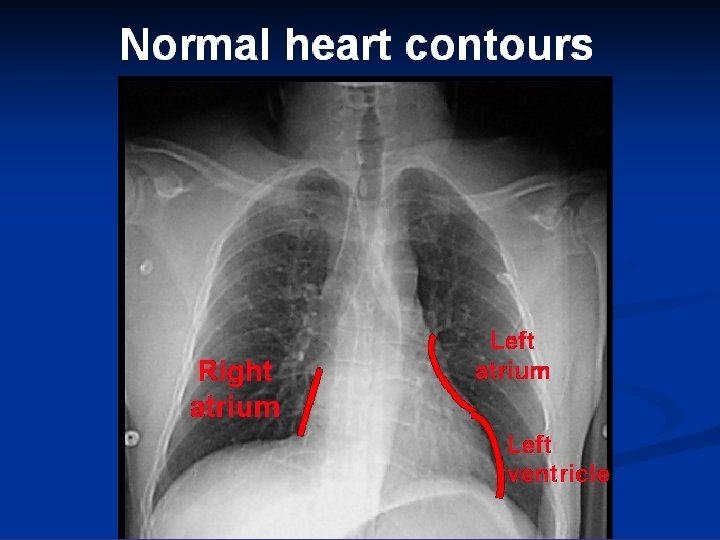

* trachea ; position & caliber * hila : lymphadenopathy * mediastinum contour : ? mass * heart : cardiac configuration Mediastinum, heart and hila

How to read a chest x ray ? • 1 - chest wall, bones and abdomen * bones; lesions or fractures * soft tissue ; mastectomy or soft tissue tumors • 2 - heart and mediastinum * trachea ; position & caliber * hila : lymphadenopathy * mediastinum contour : ? mass * heart : cardiac configuration • 3 - lungs opacity or lucency